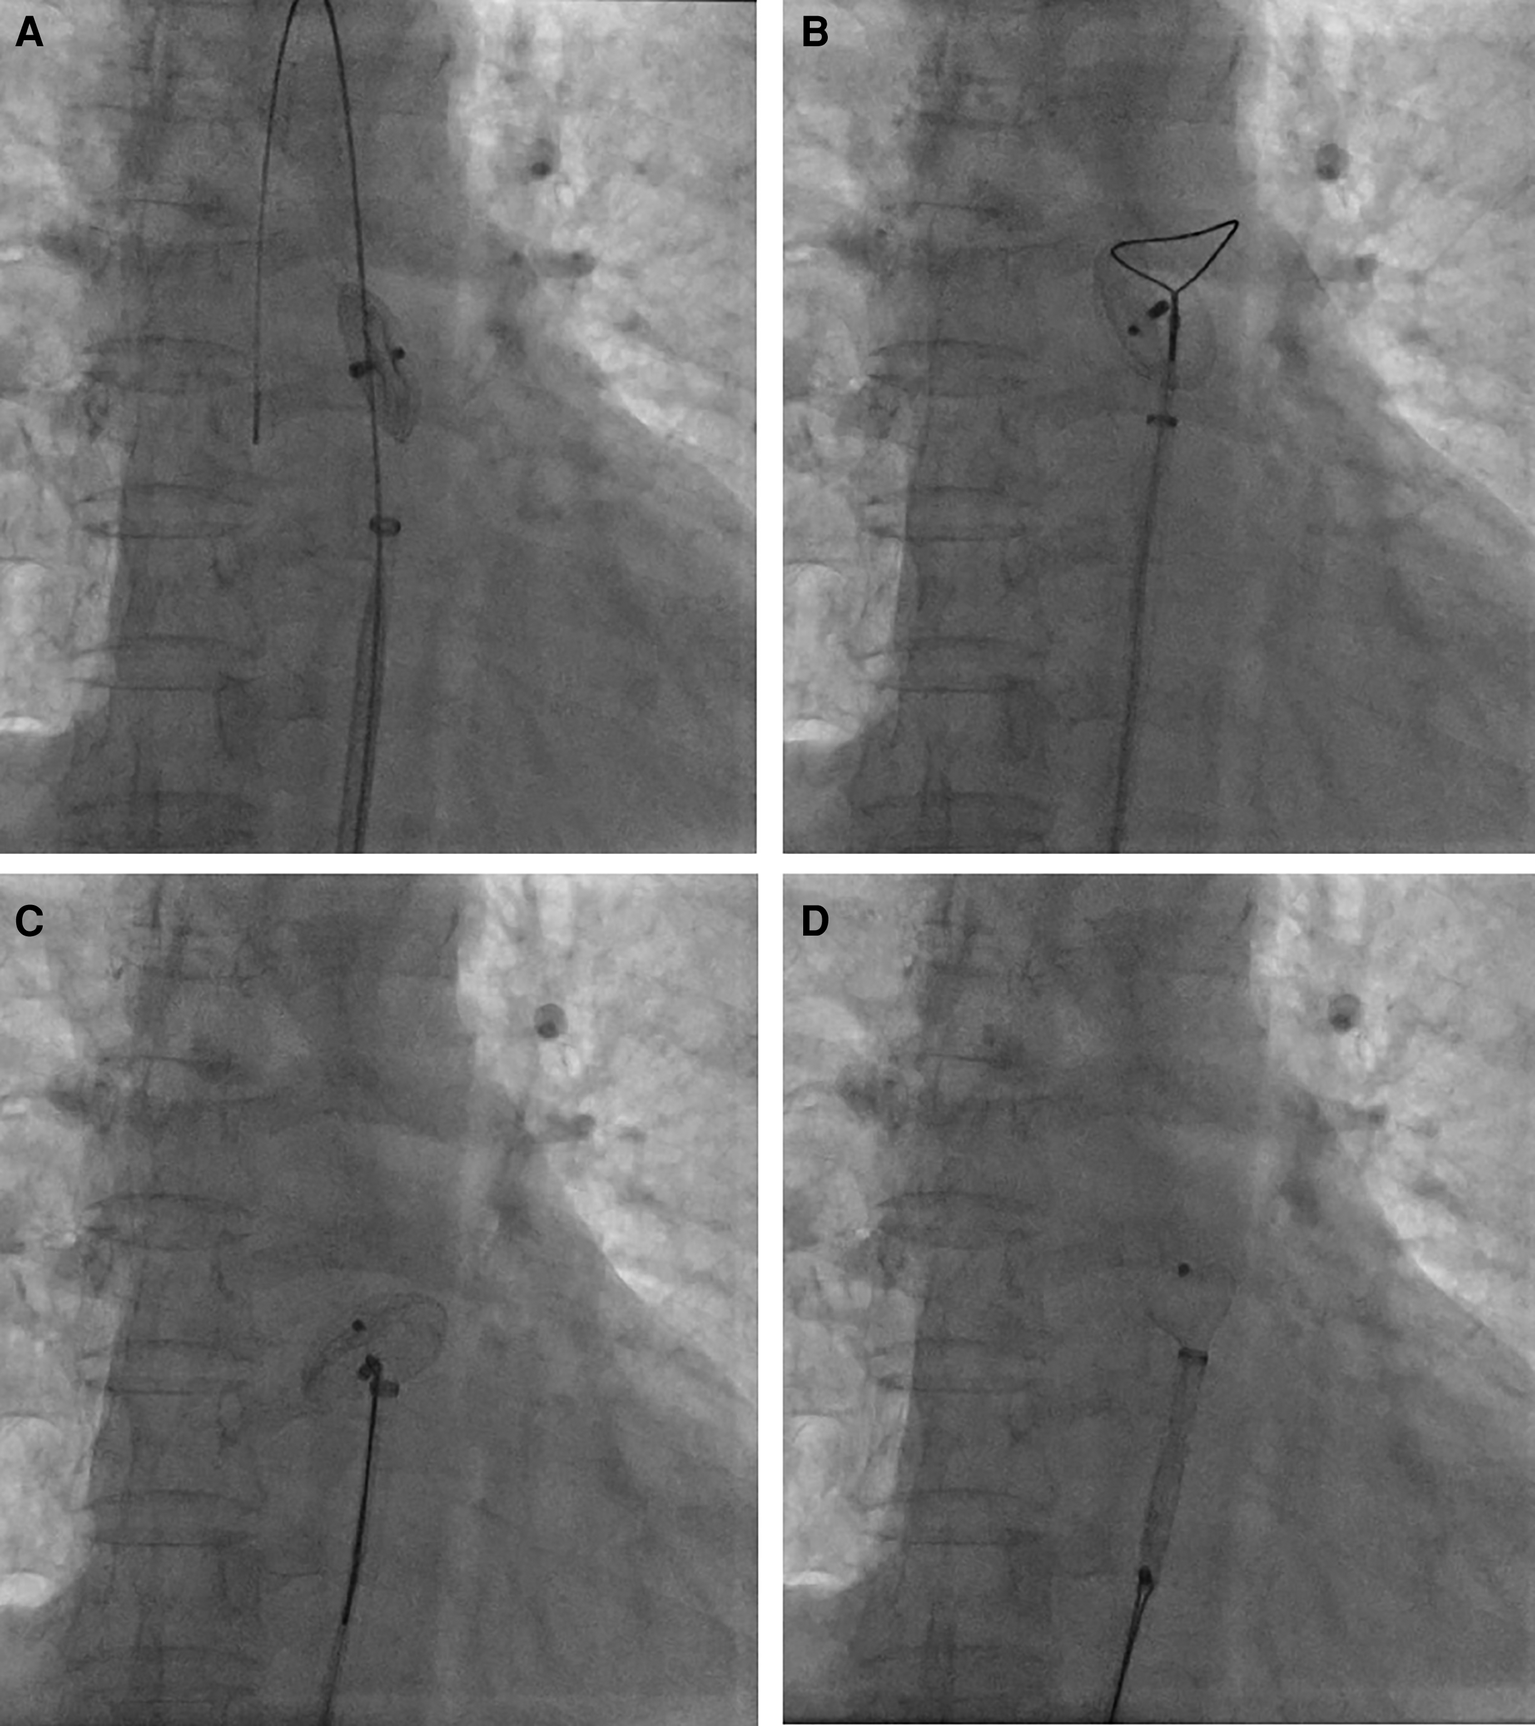

Figure 3

Percutaneous retrieval of the ASO device. Fluoroscopy revealed the embolized ASO device in the descending thoracic aortic isthmus (A); an Amplatz Goose Neck snare was advanced to the near occluder (B); after successful snaring of the screw on right atrial disc of ASO device (C), ASO device was successfully retrieved into the 12-French vascular sheath (D).

Percutaneous retrieval and redeployment were performed via puncture of the right femoral artery and femoral vein, with insertion of 6F and 8F vascular sheaths, respectively. Chest fluoroscopy confirmed the embolization of the occluder device to the descending thoracic aortic isthmus (Figure 3A). Using a 12-French vascular sheath inserted through the right femoral artery, an Amplatz Goose Neck snare kit device was advanced to the embolized site (Figure 3B). The pedicle of the occluder was exposed by adjusting its position, allowing successful capture by the Amplatz Goose Neck snare under fluoroscopic guidance (Figure 3C). The displaced occluder was pulled into the vessel sheath (Figure 3D) and ultimately removed from the body through the puncture site in the right femoral artery. A 14-French vascular sheath was inserted at the right femoral vein puncture site and guided successively through the inferior vena cava, right chamber, left atrium, and left upper pulmonary vein. Subsequently, a 26 mm occluder was advanced into the left atrium using the long vascular sheath, and both sides of the occluder were successfully deployed on either side of the defect (Figure 4A). Chest fluoroscopy confirmed the optimal position and shape of the redeployed occluder, with no residual shunt (Figure 4B). The operator performed the “Minnesota wiggle” maneuver to ensure a secure position of the occluder device. However, during the procedure, the patient experienced an intraoperative cardiac arrest, which was promptly managed through cardiopulmonary resuscitation, leading to the recovery of vital signs. Subsequently, angiography of the aorta and pulmonary arteries revealed no evidence of dissection, extravasation, or residual shunt.